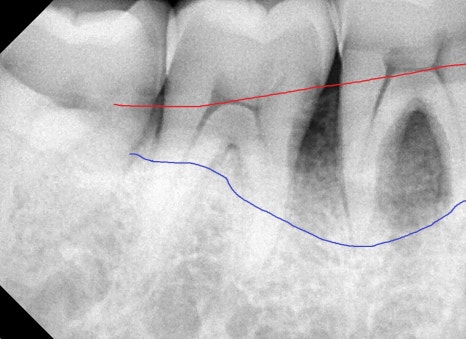

사진에서도 빨간선까지가 정상 잇몸뼈의 높이라면

위 환자분의 뼈는 이미 치주염으로 인해 파란선까지 내려앉은 걸 확인할 수 있었고

그 틈으로 음식물, 치태가 쌓이며 피도 나고 잘 붓습니다.